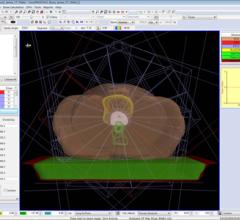

September 19, 2012 — Elekta recently announced the latest production release of its Monaco treatment planning system, Version 3.20, which offers customers improved VMAT (volumetric modulated arc therapy) planning and delivery support, in addition to support for Elekta's Agility 160-leaf multileaf collimator (MLC).